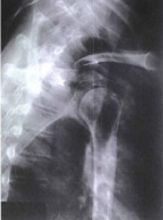

is this a normal or dislocated shoulder? how do you know?

normal, head of humerus superimposed over base of Y